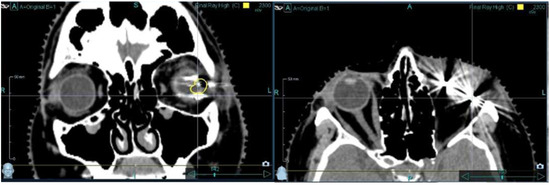

3.2. Imaging-Related Findings